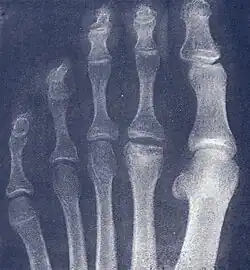

| Freiberg disease as seen on plain film | |

- Radiography: X-rays may reveal flattening, sclerosis, or fragmentation of the metatarsal head.